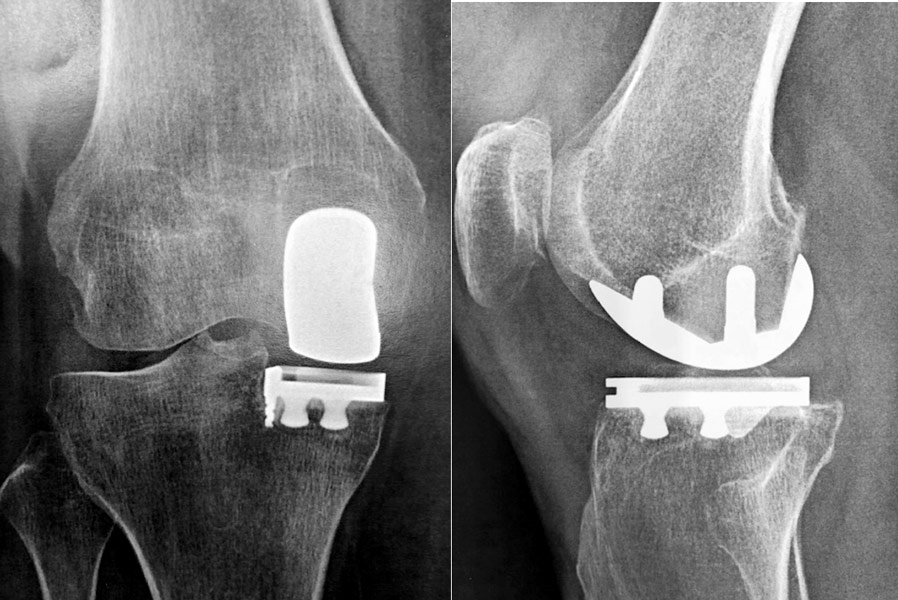

Homme 60 ans, opéré par prothèse rotulienne et prothèse uni-compartimentale interne. Toujours douloureux.

Pas d’infection.

Changement pour mettre en place une prothèse totale du genou. Aucune douleur résiduelle.

Femme de 88 ans, opérée par prothèse totale du genou NexGen à droite il y a 19 ans et à gauche il y a 18 ans.

Aucune douleur, aucune usure.

La courbe de survie de la prothèse NexGen dans les registres Australien et Anglais est de 98% à 11 ans de recul.